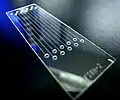

Microfluidics-assisted FISH (MA-FISH) uses a microfluidic flow to increase DNA hybridization efficiency, decreasing expensive FISH probe consumption and reduce the hybridization time. MA-FISH is applied for detecting the HER2 gene in breast cancer tissues.[22]

Another schematic of FISH process. Microfluidic chip that lowered the cost-per-test of FISH by 90%.

Microfluidic chip that lowered the cost-per-test of FISH by 90%. Dual label FISH image; Bifidobacteria Cy3, Total bacteria FITC.